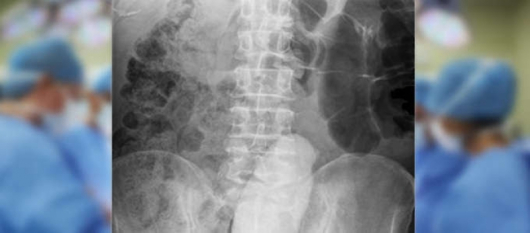

43884 прочитаЛекарите останали с отворени уста след странната находка в седалището на 68-годишен мъж, вибратор дълъг 23 сантиметра, бил проникнал много във вътрешността на мъжа и създавал предпоставки за тежкото състояние,пише италианския Тудей. Мъжът пенсиониран военен, търпял болките от декември миналата година. След оперативна интервенция, животът му е спасен.